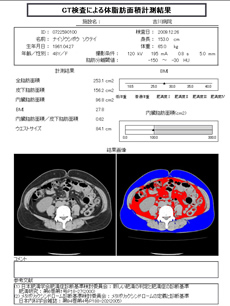

内臓脂肪測定・・・腹囲だけじゃダメ?

腹部CT検査で「隠れ肥満」もすぐ見つかる内臓脂肪測定がおこなえます。

脂肪と言えば指でつまめる皮下脂肪を想像しますが、実は体の表面からは見えない内臓脂肪が生活習慣病の原因になっているんです。最近TV・CM等メディアにおいてもこの内臓脂肪を減らそう!と盛んになっていますね。

腹囲測定のみでは姿勢、骨格の大きさ等に大きく作用されて、正確な内臓脂肪の測定はできません。

日本内科学会では、CTによる測定がより望ましいと推薦しております。一度自分の体の中をチェックしてみませんか?

左のカラーの測定結果を見てみましょう!

青色部分が皮下脂肪

赤色部分が内臓脂肪になります。

分かり易いですね。

当院では、CT装置にてお臍(ヘソ)部を1枚のみ撮影し、解析ソフトを用いて内臓脂肪量の測定をしております。

※健康保険は使用できませんので、自費扱いになります(検査料金 : 3,500円)。ご希望の方は、受付時もしくは診察時にお申し付けください(腹部のCT検査を施行する方・・・追加2,000円で内臓脂肪測定も行えます。)